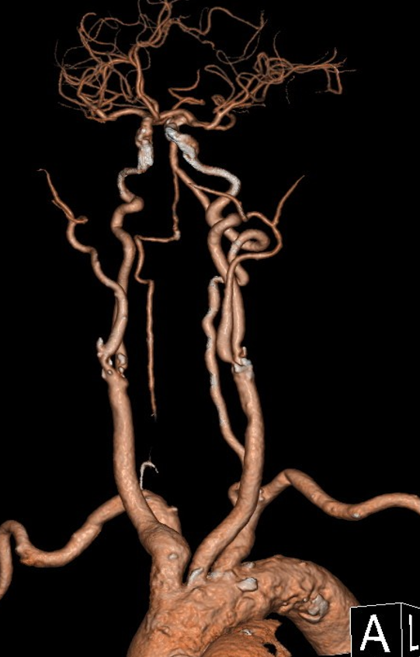

CASE 1:79岁男性,双侧颈动脉重度钙化狭窄,采用IVL预处理后置入支架,术后造影显示管腔通畅。

双侧颈动脉重度

钙化狭窄

IVL后管腔

获得良好

术后造影

显示管腔通畅